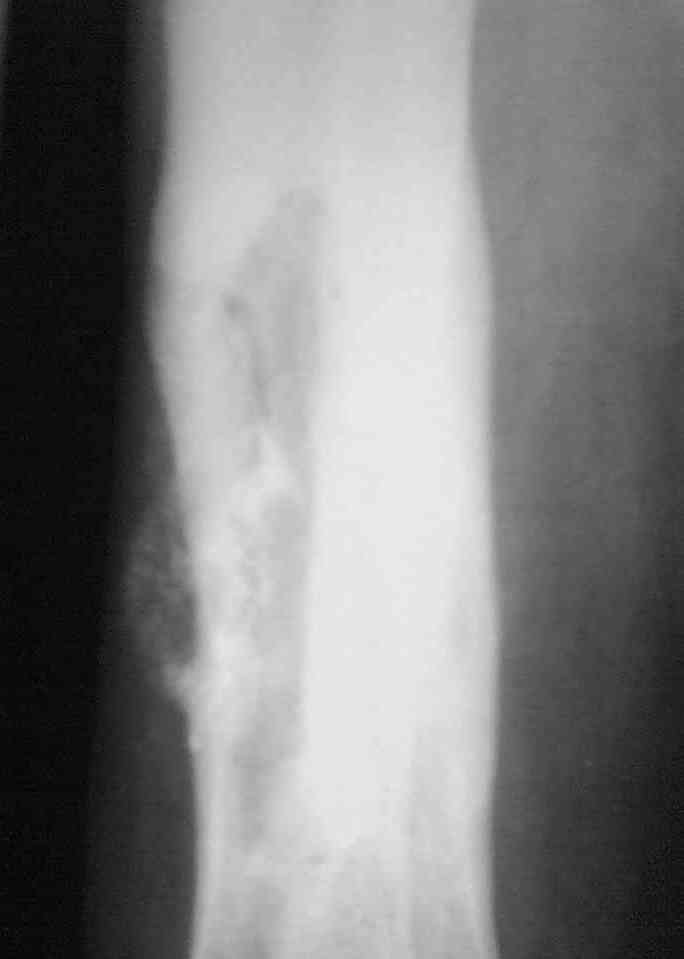

Здравствуйте коллеги! Прошу помочь с лечением больного. Мужчина в полном расцвете сил в апреле 2004 года получил травму - открытый оскольчатый перелом голени. Через 2 дня произведён МОС большеберцовой кости пластиной АО и винтами. Послеоперационный период осложнился остеомиелитом. Через 3.5 месяца пластина удалена. В марте 2005 года оперативное лечение в г. Екатеринбурге - санирование очага, некрэктомия. В июне 2006 года в ОКБ произведена секвестрэктомия, через неделю некрэктомия. Неоднократно получал антибактериальную терапию, в результате чего сформировалась сенсибилизация ко многим антибактериальным препаратам. В данный получает перевязки. Локально сохраняется кратерообразная гнойная рана, размерами до 4 х 3 см. Хотелось бы узнать Ваши мнения по поводу дальнейшего ведения данного пациента.

Выкладываю снимки в хронологическом порядке. Снмки все какие есть у больного.

Количество не заменяет качества, поэтому не стоит выкладывать весь хлам, какой удастся найти у пациента. Лучше сделать 1)свежие 2)хорошего качества рентгенограммы, чтобы оценивать ситуацию по ним, а не по мутным огрызкам.